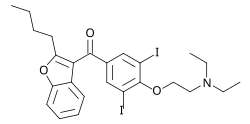

Um eine optimale Aufnahme des Jods in die Schilddrüse zu erreichen, sollen vor dem Radiojodtest und der Therapie mit radioaktivem Jod zusätzliche Jodquellen gemieden werden (Jodkarenz). Solche Jodquellen sind insbesondere jodhaltige Kontrastmittel, das Antiarrhythmikum Amiodaron und bestimmte jodhaltige Desinfektionsmittel. Bei wasserlöslichen Kontrastmitteln reicht eine Karenzzeit von 6 Wochen. Nach der Anwendung fettlöslicher Kontrastmitteln oder des ebenfalls fettlöslichen Amiodaron kann die Schilddrüse für viele Monate blockiert sein.